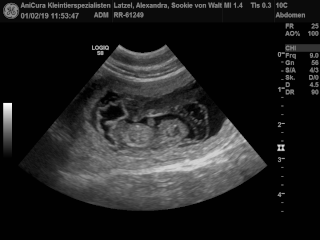

| 01.02.2019 |

Sookie und Uaine erwarten Babies! Die Ultraschallbilder beweisen es! Hier sind die Bilder!!! |

| Hier sind die Ultraschallbilder von Sookie von Waltenweiler!!! |